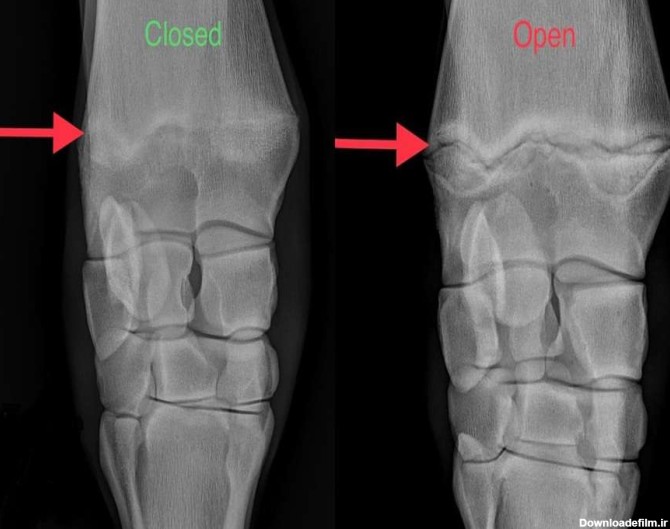

داشتن قد بلند آرزوی بسیاری از افراد است. افراد بسیاری برای رسیدن به این خواسته در سنین رشد به پزشک مراجعه می نمایند و خواستار این هستند که با روش های قد خود را افزایش دهند. رادیوگرافی ساده استخوان های مچ دست تجویز پزشک در این مواقع برای شماست. در واقع پزشک با مشاهده عکس مچ دست، سن استخوانی را تشخیص میدهد و میفهمد که آیا صفحه رشد استخوانهای فرد باز است و هنوز جای رشد دارد یا نه؟ در صورتیکه اگر سن استخوانی فرد بالا باشد و صفحه رشد بسته شده باشد، دیگر جایی برای رشد طولی استخوانها نخواهد بود. در انتهای استخوانها صفحهای به نام اپیفیز وجود دارد که در سنین رشد از جنس غضروف است و با تاثیر از هورمون رشد غضروفسازی میکند. با گذشت زمان این...

صفحه رشد چه کاری انجام می دهد؟ - علائم بسته شدن صفحه رشد - علائم صفحه رشد بسته - افزایش قد بعد از بسته شدن صفحات رشد چجوری ممکن است؟ + عکس صفحه رشد باز و بسته

صفحه رشد، محل رشد استخوان جدید در کودکان هست.که این صفحات در دختران در سن 15 و پسران در سن 17 سالگی بسته میشوند اما استثنا نیز وجود دارد...